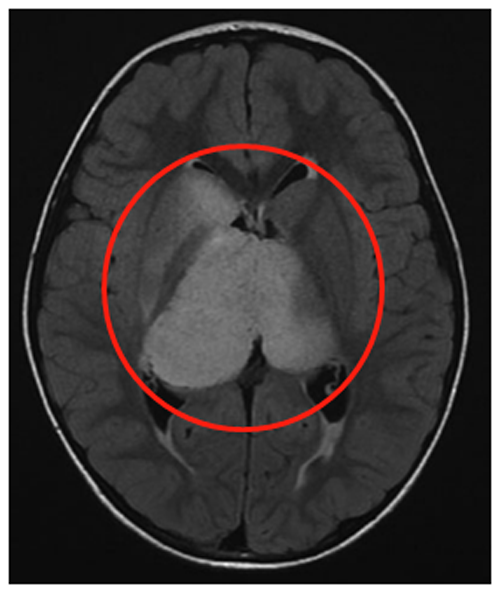

病史回顾:头痛成为6岁的星星(化名)挥之不去的“梦魇”,随之而来的,还有间歇性的左半边上身震颤。检查结果同样不容乐观:两侧丘脑竟长了“橘子”般大的肿瘤,右边甚至更大,尾状核的右头部也被牵连,肿瘤已经导致脑室轻度增大、膈膜水肿等,且肿瘤内部囊肿明显。